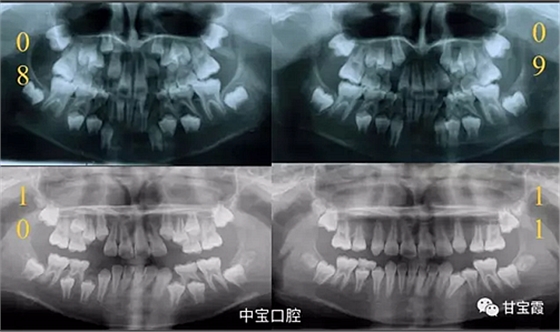

有一個七歲的小女孩,在替牙時媽媽發(fā)現(xiàn)孩子新長的牙不整齊,有一顆長到里面了,上下頜中線也不對稱,很著急就來到門診看牙。

經(jīng)過我臨床檢查和X線的診斷,決定早期干預,每三個月定期復診檢查一次,并拔掉了幾個乳牙和四個恒牙,正畸專業(yè)叫序列拔牙。

經(jīng)過三年零九個月的看護,最終戴上了固定矯治器,但是大家不難發(fā)現(xiàn),孩子的牙齒已經(jīng)排齊,上下中線也基本對齊,面型也好看多了,這樣矯正就變得簡單,療程自然縮短,孩子也不遭罪了。

這個故事告訴我們,只有家長早點把孩子帶給正畸醫(yī)生檢查,才能早期發(fā)現(xiàn)早期治療。起到了事半功倍的效果。矯正以后還不容易復發(fā),因為從08年的初診到11年戴矯正器這三年多的時間里,孩子的牙齒是自己長好的。